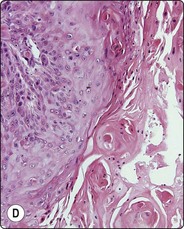

image

Fig. 4.24 Cystic salivary gland neoplasms

(A) Cystic Warthin’s tumor (macro); (B) Cyst fluid from same lesion with a single small group of bland oncocytic epithelial cells (Pap, IP); (C) Predominantly cystic pleomorphic adenoma (tissue section, H&E); (D) Cystic mucoepidermoid carcinoma with small tumor nodules in the cyst wall (tissue section, H&E). The fluids aspirated from (C) and (D) were practically acellular.

Cystic neoplasm is the most important differential diagnosis of non-neoplastic salivary gland cyst. The majority of cysts occurring in the major salivary glands are, in fact, associated with neoplasms, which may be benign or malignant. Warthin’s tumor and low-grade mucoepidermoid carcinoma are the commonest, but pleomorphic adenoma, cystadenoma, acinic cell carcinoma and other tumors may also be predominantly or partly cystic (Fig. 4.24). Aspirated fluid from a cystic neoplasm is often poor in cells and indistinguishable from fluid from a non-neoplastic cyst. If the lesion disappears completely after evacuation of the fluid, it is most likely of non-neoplastic nature. However, any remaining solid part must be biopsied. US guidance is helpful in this situation, particularly because the cyst may refill with blood following the initial FNB, rendering the solid portion impalpable. Clinical follow-up of cystic salivary gland lesions is essential if a specific diagnosis cannot be made.